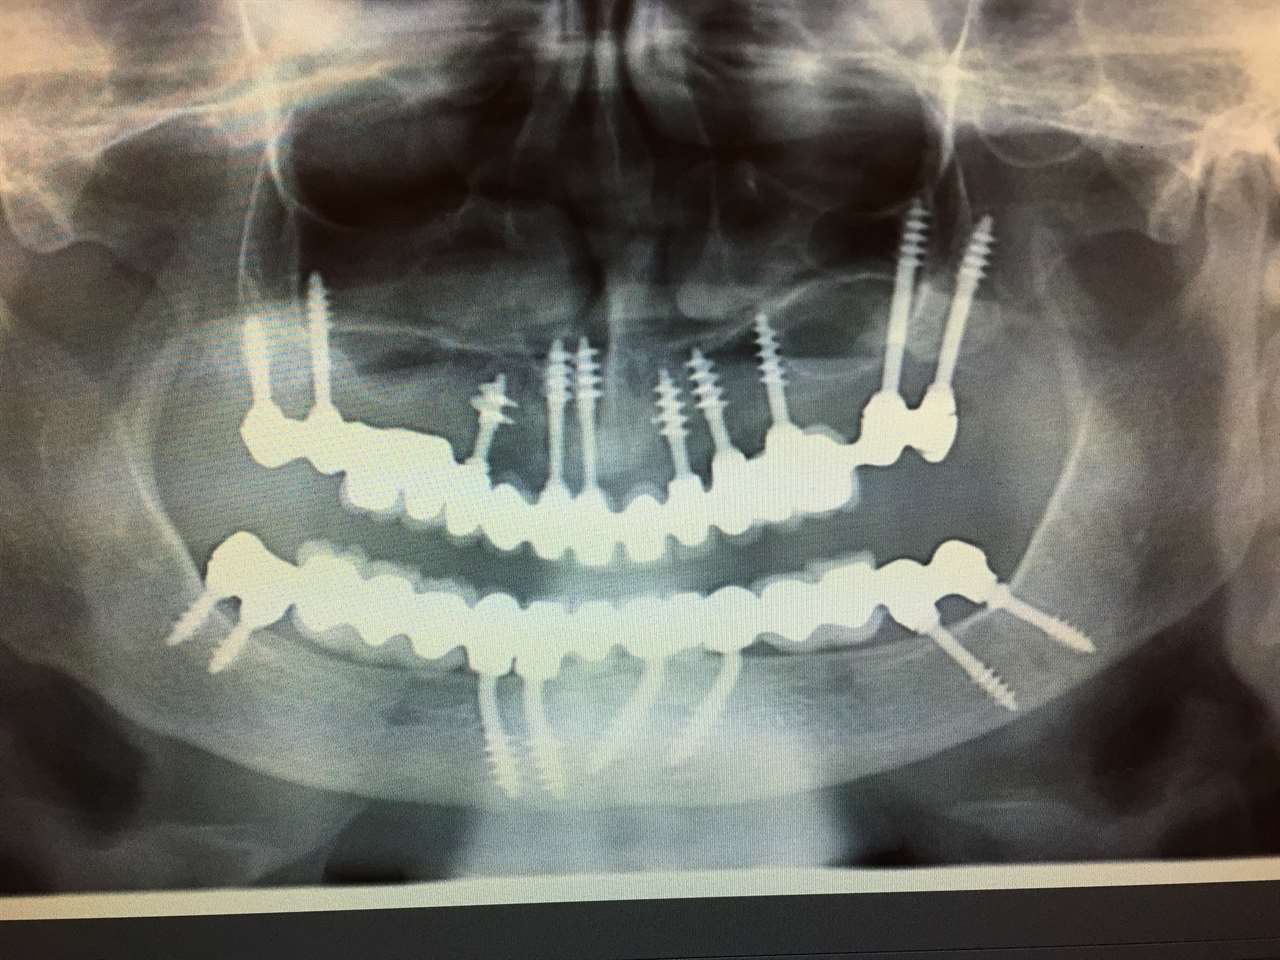

Elhanyagolt fogsor cseréje 2 nap alatt

2 nap alatt varázsoltuk ezt a szép esztétikus alsó, felső körhídat implantátumokkal megtámasztva a korábban elhanyagolt szájba. Az 1. nap 26 fogat távolítottunk el, mert annyira rossz állapotban voltak, és rögtön azonnal terhelhető IHDE svájci implantátumokat raktunk be, fentre 8, lentre 6 darabot. A sebeket összevarrtuk és intraorális szkennerrel digitális lenyomatot vettünk. 2 nap múlva pedig beragasztottuk a kész PMMA műanyag körhidakat. Dr. Kelemen Péter és a Symbion Fogtechnika munkája.